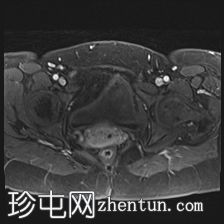

轴位T1加权像

脂肪抑制像

增强脂肪抑制像

可见膀胱左侧壁有一边界清晰的T2低信号实

性病

灶,无扩散受限,均匀强化。未见膀胱周围侵犯或肾积水。

子宫底部前壁可见一小肌瘤。双侧卵巢可见无强化囊肿。盆腔及腹股沟未见异常淋巴结肿大。

这是一例经组织学证实的膀胱平滑肌瘤病例。